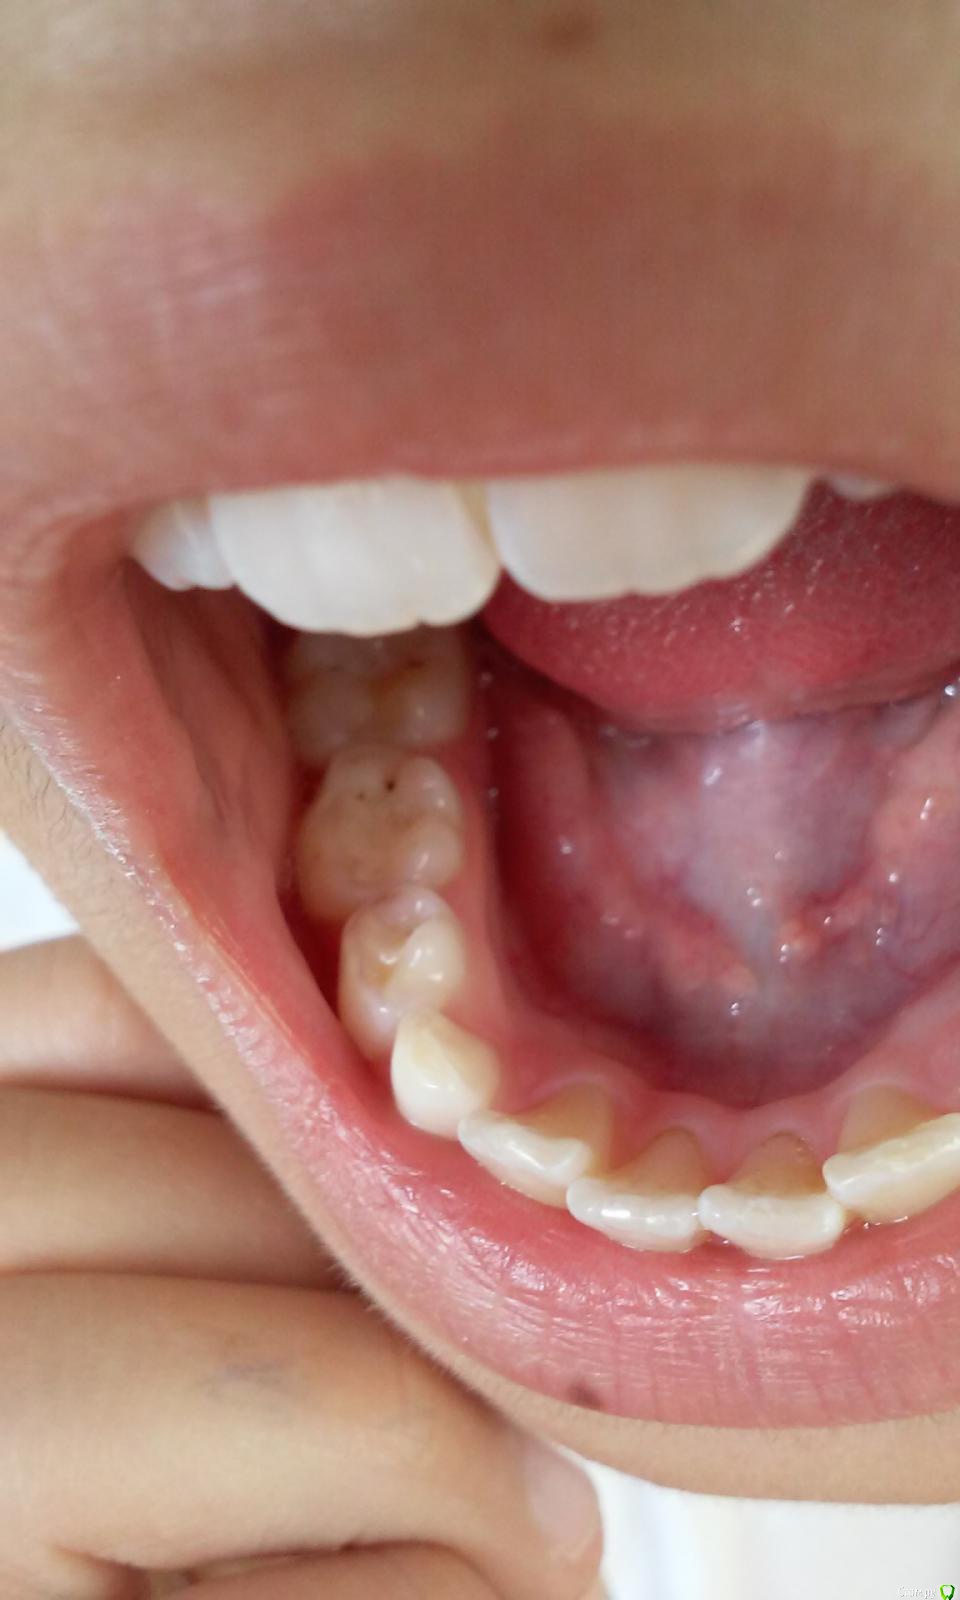

Маргарита1234 Опубликовано 3 октября, 2015 Поделиться Опубликовано 3 октября, 2015 Здравствуйте, уважаемые стоматологи! Очень прошу о помощи. У дочери 9 лет на постоянных зубах на верху и внизу черные единичные точки, а также бороздочки сбоку зуба, меня это тревожит, 1 раз в 6 мес. делаем в поликлинике кальцинирование, затем фтором покрываем, всегда тщательно следили за зубами, врач сказала, что это не кариес и удалять не нужно,т.к. могут вновь появиться. Проверили у лора, обнаружили золотистый стафиокок, лечим, проверяемся у гастроэнтеролога, но от чего такие бороздочки на зубах???? Что делать, какие анализы сдавать. И ещё, наносим сами гель Рокс. Ссылка на комментарий

red_butler Опубликовано 3 октября, 2015 Поделиться Опубликовано 3 октября, 2015 Похоже на кариес 1 Ссылка на комментарий

Джима Опубликовано 4 октября, 2015 Поделиться Опубликовано 4 октября, 2015 (изменено) там герметик что ли? герметизировали фиссуры? в нижнем зубике мне похоже как по краю герметика либо пигментация фиссуры, либо уже кариес. в верхнем - скорее всего небольшой кариес. но по фото однозначно не скажешь Изменено 4 октября, 2015 пользователем Джима Ссылка на комментарий